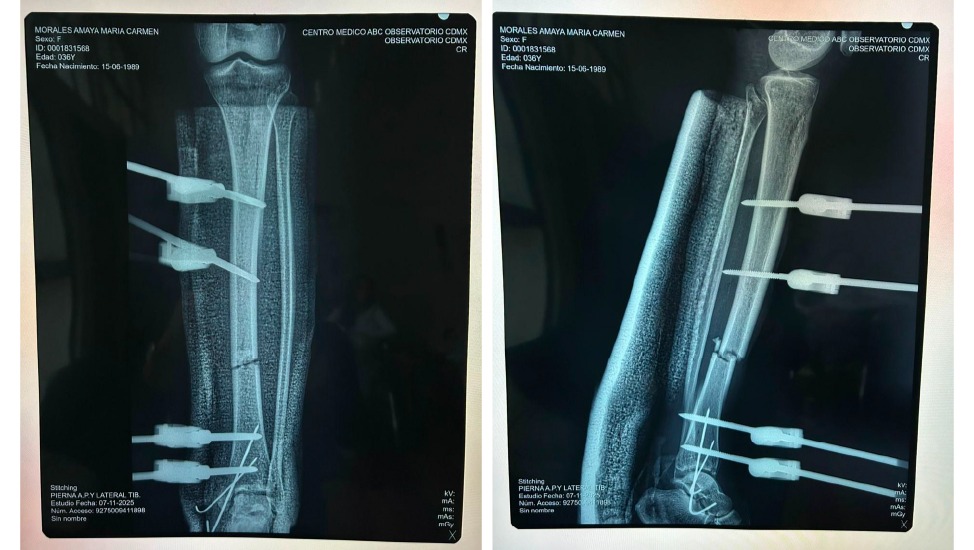

Aunque ya está fuera de peligro, una de sus fracturas no está evolucionando como debería y eso pone en riesgo su recuperación. La tibia izquierda, que fue fractura expuesta, fue inmovilizada con tutores el día del accidente.

En una revisión reciente, con segunda opinión incluida, los médicos detectaron que la recuperación no progresa como se esperaba. Su tobillo ha estado más de dos meses inmovilizado con una férula, lo que le ha provocado úlceras por presión y zonas de tejido muerto que hay que limpiar para evitar una infección severa.

Maca no puede sostener ni flexionar el pie por sí sola, lo que indica un posible daño neurológico que hay que estudiar a fondo.

Cirugía de tibia izquierda: Reducción abierta de la fractura con colocación de clavo intramedular o placas, tornillos e injerto óseo para fijar correctamente el hueso y darle a Maca la mejor oportunidad posible de recuperar la movilidad de la pierna.